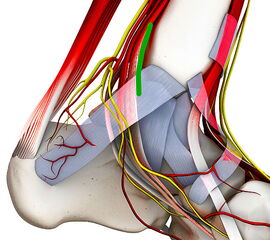

Abbildung 2: K-Draht Spreizer. Dieser erlaubt eine Distraktion des Gelenks über 1,8 mm Kirschnerdrähte. Diese Technik hilft in nahezu allen Fällen eine Innenknöchelosteotomie zu vermeiden.

Abbildung 2

• Sprunggelenk Basisinstrumentarium.

• Spreizer mit Bohrungen für Kirschnerdrähte (Abbildung 2).